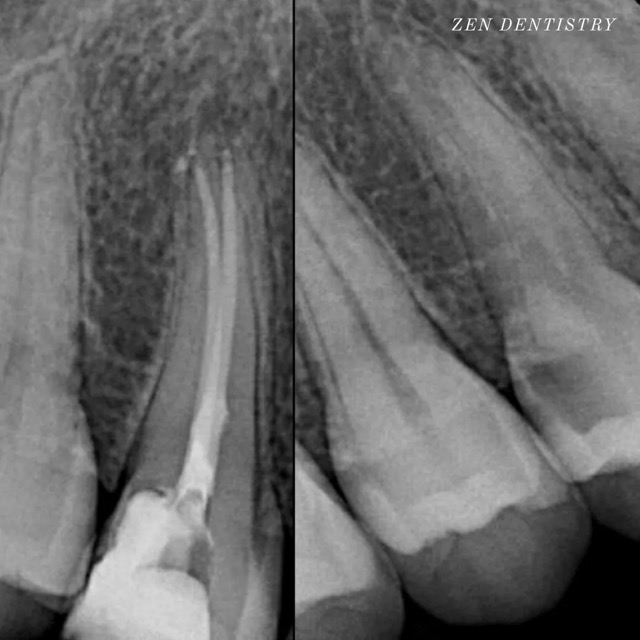

Patient presented to the office with trauma to front two teeth several weeks ago causing her severe pain. After a thorough clinical exam which included endodontic screening and proper x rays led to the diagnosis of necrotic (dead) pulp tissue due to the force of trauma.

Root canals were performed and highly aesthetic Emax crowns were fabricated to meet the patient’s desire to maintain the natural smile and contour as was before the trauma.